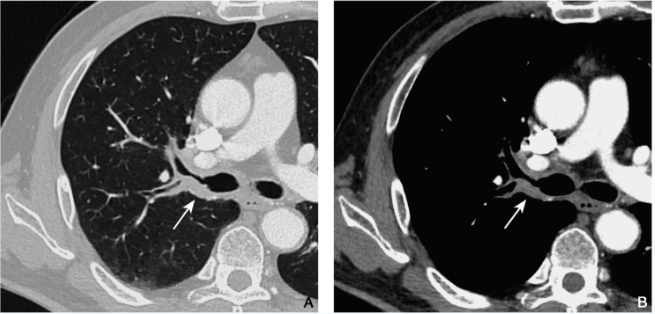

图2 浸润性鳞癌

男性,69岁,咳嗽伴痰中带血1个月就诊,术前增强CT肺窗(A)及纵隔窗(B)示右肺上叶支气管管壁增厚(箭),以支气管后壁为著